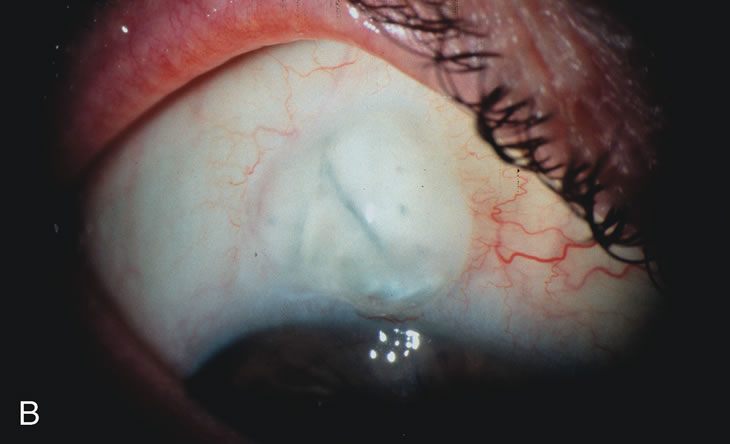

Cataract extraction by any technique performed in a patient with a pre-existing filter will have an effect on the previous filtering bleb.121–124 Bleb failure is more likely with ECCE compared with small-incision phacoemulsification.125 However, even patients undergoing topical anesthesia with clear corneal phacoemulsification and foldable IOL may experience bleb failure. One of three patients with a functioning filter and preoperative mean IOP of 12 mm Hg without antiglaucoma medications experiences bleb failure after lens extraction (Table 2). These patients require long-term drug therapy or bleb needling to control IOP. 126 Additional incisional glaucoma surgery may eventually be required in up to 10% of patients.127 Intraoperative iris manipulation may cause significant breakdown of the blood–aqueous barrier, resulting in inflammation that causes bleb failure. Even after uncomplicated clear corneal phacoemulsification, IOP may increase an average of 2 to 3 mm Hg due to bleb fibrosis.128 Approximately 20% of filtered patients require a long-term increase in glaucoma medications following uncomplicated clear corneal phacoemulsification with a foldable copolymer acrylic IOL129 (Fig. 3). In situations in which the bleb is not working at all, the eye will have a postoperative pressure spike that mimics that in the patient not having had a prior filtering procedure. In situations in which the bleb is marginal, the pressure spikes tend to be lower, and the final postoperative IOP tends to be around 50% higher than it was preoperatively. These patients require combined procedures in order to reestablish long-term filtration. In situations in which the bleb is very thin, polycystic, and associated with an IOP around 5 to 8 mm Hg on no antiglaucoma therapy; uncomplicated cataract extraction will have a minimal effect on the level of IOP. Patients with functioning glaucoma drainage implants usually have minimal long-term changes in IOP after uncomplicated cataract extraction.130

Fig. 3. Partial bleb failure following clear corneal phacoemulsification with foldable IOL. A. Preoperative bleb appearance prior to temporal lens extraction. Preoperative IOP was 12 mm Hg on no antiglaucoma medications. Time from 5-FU trabeculectomy surgery to lens extraction was one year. B. Bleb appearance 2 months after clear corneal cataract surgery with topical anesthesia. Following lens extraction, increased vascularity was noted along with decreased size of the filtering bleb. IOP increased to 20 mm Hg as early as 2 weeks after surgery, necessitating topical antiglaucoma therapy. C. High magnification view of bleb before lens extraction demonstrates diffuse pale bleb. D. High magnification view of bleb 2 months after surgery. There are vessels surrounding the nasal side of the bleb and the overall bleb size is smaller.